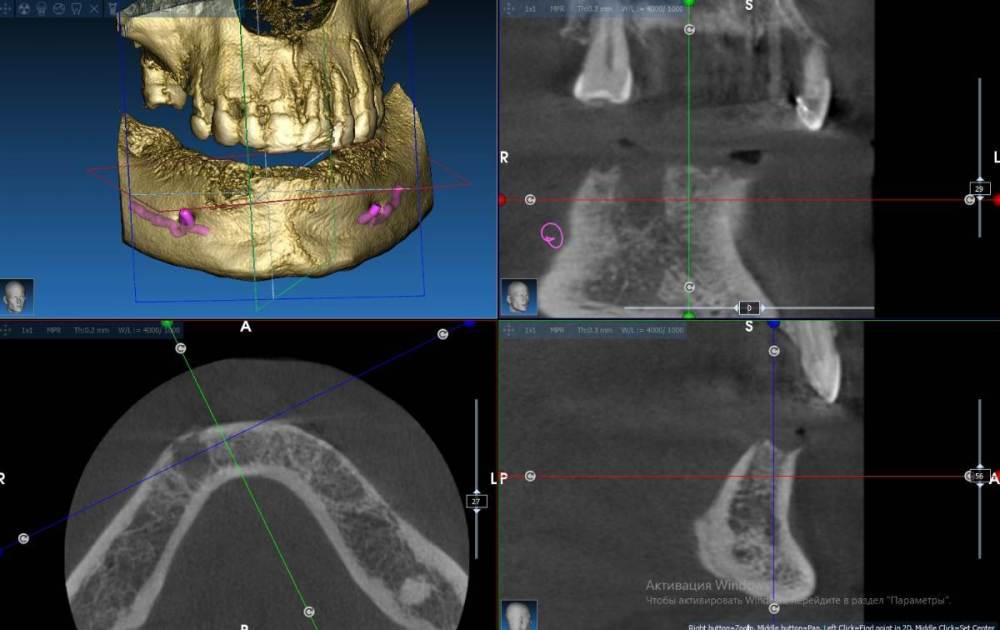

Fin Опубликовано 13 марта, 2022 Поделиться Опубликовано 13 марта, 2022 Здравствуйте коллеги. Появился очень странный вопрос. Год назад у меня был пациент - мужчина 40 лет на консультацию по имплантации все на 6 на НЧ. В процессе осмотра снимка КТ обнаружил в зоне 43 хронический воспалительный процесс. Данный процесс был прокюретажен, пациент отпущен на заживление на пару месяцев. Старый снимок Так получилось что с пациентом мы встретились только сейчас и решили продолжить наше лечение. Далее повторное КТ со скан маркерами на его съемном протезе, сделан слепок протеза- пациент отпущен. В ходе планирования шаблона я обнаружил улучшение со стороны воспалительного процесса но так же обнаружил странное образование рядом не сообщающееся со старым воспалением. Новый снимок Подскажите что это может быть т.к. вижу такое впервые. Сам думаю что скорее всего я преувеличиваю и это из-за того, что снимки сделаны на разных аппаратах, но хотелось бы услашать Ваше мнение. Ссылка на комментарий

Doctor Vlad Опубликовано 14 марта, 2022 Поделиться Опубликовано 14 марта, 2022 кортикалки то не стало в стороне от лунки. может и стоит Ссылка на комментарий

Fin Опубликовано 14 марта, 2022 Автор Поделиться Опубликовано 14 марта, 2022 3 часа назад, Doctor Vlad сказал: кортикалки то не стало в стороне от лунки. может и стоит Меня это и удивило, видимо да, все таки отправлю пациента в ЧЛХ Ссылка на комментарий